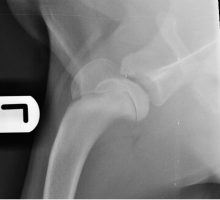

Total Hip Replacement Surgery

Total hip replacement at Eastcott Referrals Swindon During the last 5 years, we have developed a well-established total hip ...

Hip Replacement Surgery

Total Hip Replacement Surgery in Dogs We are now offering total hip replacement using the well-developed and successful Biomedtrix ...